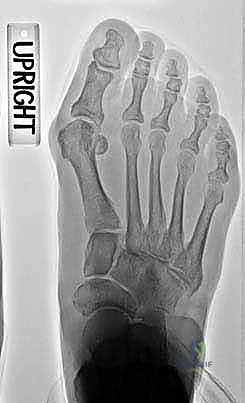

2. التصوير الشعاعي المتقدم: أخذ صور أشعة سينية للقدم أثناء الوقوف (تحميل الوزن) من زوايا متعددة لقياس زاوية إبهام القدم (HVA) والزاوية بين المشطين (IMA) بدقة متناهية.